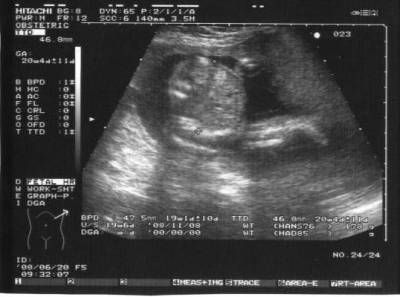

Megjöttem az uh-ról.

BPD: 4,3 cm

HC: 15,6 cm

AC: 13,6 cm

FL: 2,7 cm

OFD: 5,4 cm

Minden rendben vele, csak kicsit aggaszt, hogy a méhlepény hátsó fali, az alsó polusa eléri a belső méhszáj szélét.

Sajna nem tudták 100%-ra megmondani, hogy mi a neme. Az orvos szerint inkább kislány.

Szóval nem tudom, de szerintem nekünk se jött be a várvavárt nem.

4D -re augusztusban megyünk.

Naysa